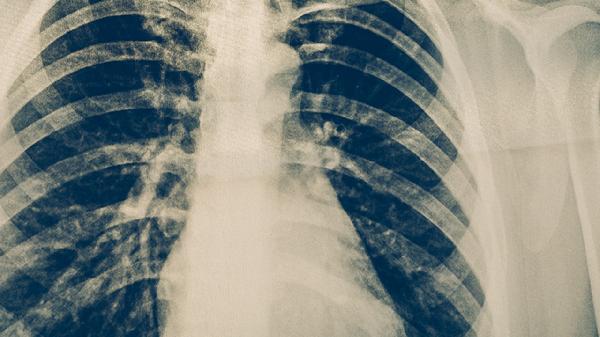

什么人容易得肺结核和肺结节

肺结核和肺结节的高风险人群主要包括免疫功能低下者、长期接触粉尘或有害气体者、慢性呼吸道疾病患者、吸烟者以及家族遗传倾向者。